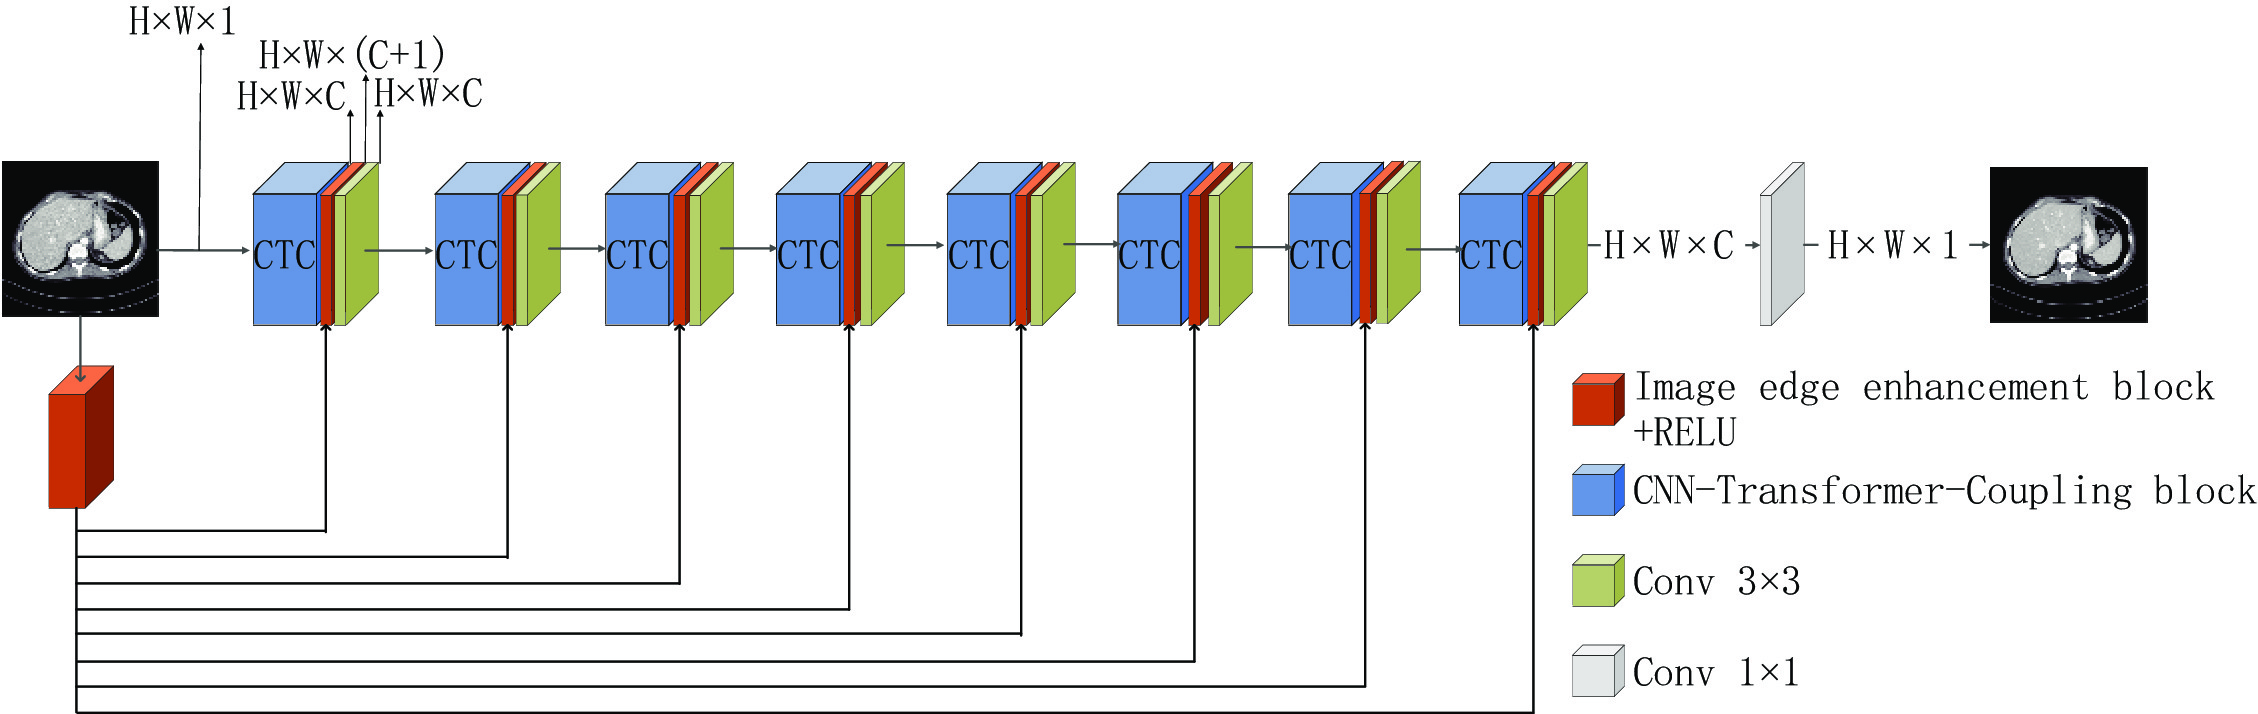

本文提出的CTC网络结构如图3所示,用于低剂量CT图像去噪。整个网络模型共有9层,其中前8层结构一致,每一层由CNN和Transformer耦合模块(CTCB)、图像边缘增强模块(IEEB)和3×3卷积层组成。输入的图像经过图像边缘增强之后,得到的特征图像通过残差连接与CNN和Transformer耦合模块以叠加通道数的方式进行融合。之后运用3×3的卷积使通道数转换为32,以保证传播过程中通道数不发生变化,目的是尽可能地保留图像的细节信息,充分利用提取的边缘信息和原始输入。运用多残差机制有效避免了因网络过深而带来的梯度消失和梯度爆炸问题,更合理的利用图像信息。

采用图像边缘增强的信息复用机制,在每一个单元与核心模块融合再利用,使图像的轮廓更加突出,保留更加完整的细节信息。网络中通道数为32,自注意力头数为2。最后一层为1×1的卷积层,将通道数转换为输出通道数,并输出图像。